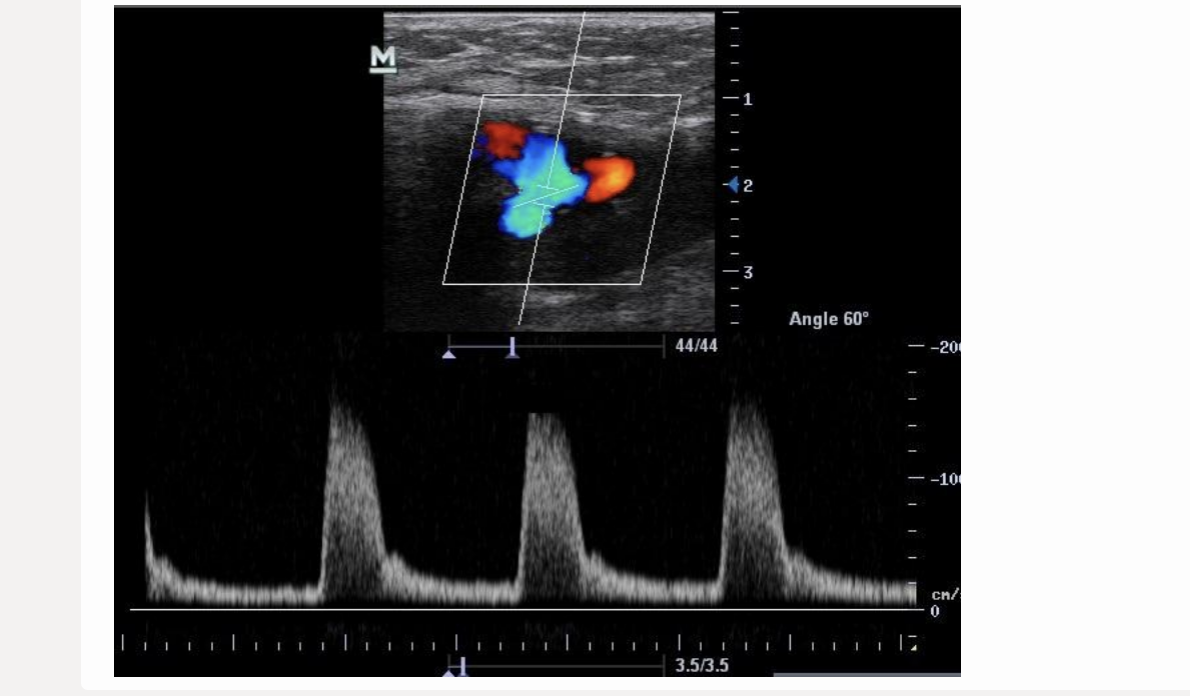

![<p>where does the 1st caliper go when measuring acceleration time? click on the 3rd waveform</p><p>.</p><p>[start of 3rd waveform]</p>](https://knowt-user-attachments.s3.amazonaws.com/10a2a0eb-5b9b-4269-8bf3-eb6e5f0a21bd.png)

where does the 1st caliper go when measuring acceleration time? click on the 3rd waveform

.

[start of 3rd waveform]

start of 3rd waveform